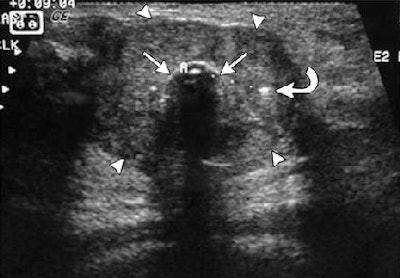

| US images. Above, transverse view of developing ice ball (< 1 cm in diameter; straight arrows) in 2.3-cm-diameter fibroadenoma (arrowheads) at initiation of freeze. Thermocouple tip (curved arrow) is 7 mm from the cryoprobe. Below, transverse view of growing ice ball (straight arrows) at two (left) and three (right) minutes, and thermocouple (curved arrow) is just becoming engulfed in ice at 6° C and -6° C, respectively. |

![]() |

"US produced excellent ice visualization beyond tumor margins, while thermocouples confirmed cytotoxic temperatures approximate 5 mm behind the visible leading edge," Littrup's group wrote. In addition, they noted that all but seven patients were able to tolerate the procedure under local anesthesia (Radiology, January 2005, Vol. 234:1, pp. 63-72).